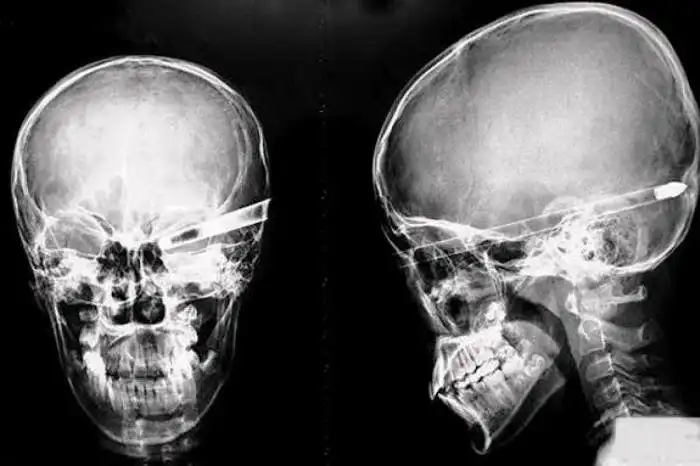

Необычные предметы в теле людей на рентгеновских снимках

На рентгеновских снимках людей порой можно обнаружить самые необычные предметы, которые находятся в их теле.